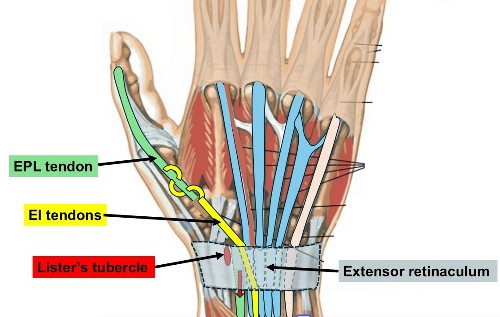

- The EPL = Extensor Pollicus Longus tendon runs along the back of the wrist to the thumb and wraps around Lister’s tubercle, using it as a pulley.

- The muscles are in the forearm. Tendons are like rope joining the muscles to the fingers and thumb. There is a strap of tissue ( extensor retinaculum) on the back of the wrist that holds the tendons down. There are 6 tunnels on the back of the wrist containing the Extensor tendons to the thumb, fingers & wrist.

- This applies particularly when the fracture involves Lister’s tubercle – a prominence on the back of the radius around which the EPL changes direction

2. EI to EPL tendon transfer.

- There are 2 tendons that extend the Index finger ( EI & EDC tendons)

- The EI tendon is available for transfer because the EDC tendon to the index finger can still provide normal index finger extension on its own

- The Extensor Indicis (EI) tendon (used to extend the index finger) is redirected to take over the function of the EPL.